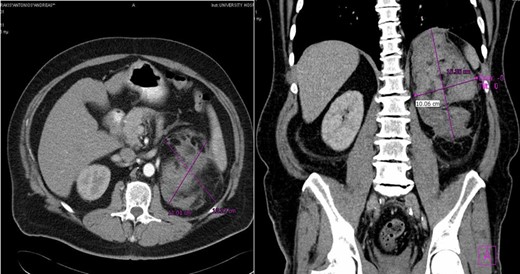

A 60-year-old male presented with pain at the left upper quadrant and left flank, radiating to the back. The patient had known hypertension and had suffered a myocardial infarction a year ago with stent insertion, now being on aspirin and clopidogrel. Upon admission all observations were normal. On examination, tenderness with guarding were noted at the left upper quadrant. Giordano sign was strongly elicited. Laboratory investigations were normal other than leukocytosis (WBC: 15.300, 89% neutrophils). US was unremarkable and CT scan revealed a retroperitoneal hematoma, at the site of the left adrenal gland, associated with extravasation of contrast (Fig. 3). The patient underwent angiography and active bleeding was confirmed from the middle adrenal artery which was successfully embolized microspheres (Fig. 4). The patient was transferred to ICU. He remained hemodynamically stable, without requiring blood transfusion. Four days later he was transferred to the ward. Pheochromocytoma was excluded with VMA, while ACTH and cortisol measurements ruled out adrenal insufficiency. Clopidogrel was permanently discontinued. The patient was discharged after 14 days and follow-up MRI confirmed hematoma resolution excluding an underlying mass.

Case 2 presenting imaging (CT) showing a large left peri-adrenal hematoma.